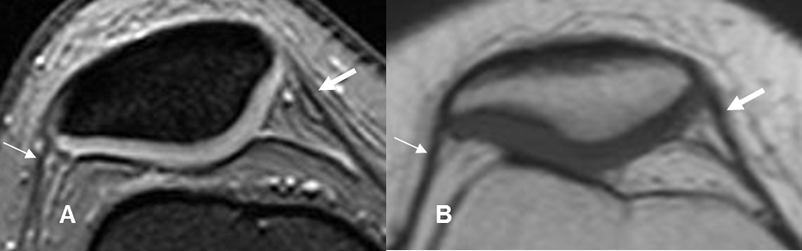

Fig 29. Meniscos normales.

A: RM sagital en T1, B: RM sagital en T2 y C: ArtroRM sagital en STIR. Meniscos normales triangulares e hipointensos en todas las secuencias. Cuernos anteriores (Flechas delgadas) y cuernos posteriores (Flechas gruesas).

Fig 30. Meniscos normales.

A: RM coronal en STIR. Menisco interno (Flecha delgada) y menisco externo (Flecha gruesa). B: RM axial en T2. Menisco interno (Flechas delgadas) y Externo (Flechas gruesas).